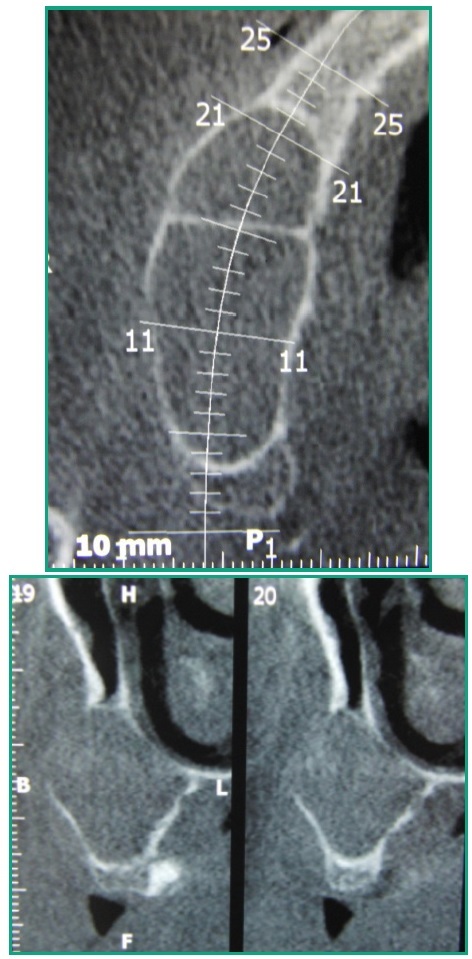

A efectos del diagnóstico y plan de tratamiento se indica una Tomografía Computada (TC), examen realizado a través de adquisición de haz cónico único de rayos X, donde se corroboran las medidas de la lesión de 40.2 mm. en sentido ántero posterior por 30.1mm en sentido vertical. En todos los cortes tomográficos se observa que el seno maxilar derecho está ocupado por una lesión, con un tabicamiento a la altura del 13, que no deforma la pared nasal del seno maxilar (Figs. 4, 5).